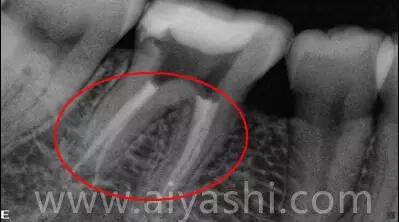

通过一组病例来了解下:

- 术前X光片:红圈处清晰显示牙体龋坏,已影响牙髓,需做根管治疗

- 术后X光片:显微镜下热牙胶根管治疗后,可见充填严密到位